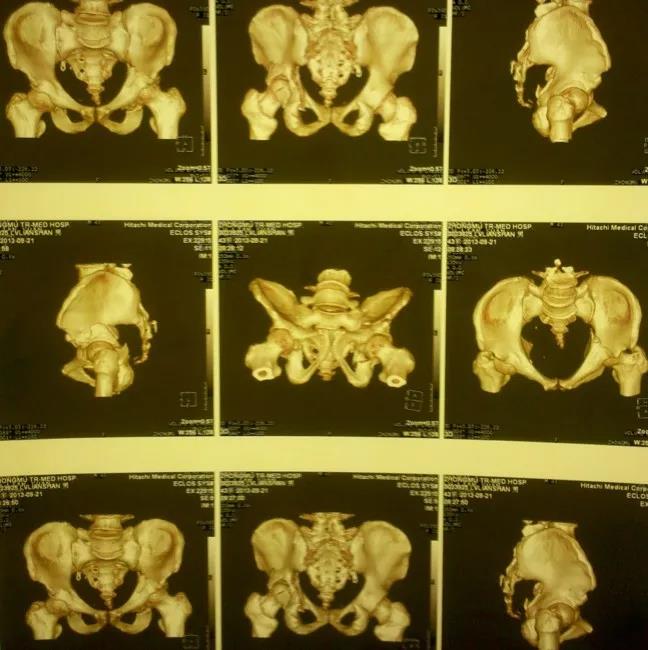

——典型案例——

微创插板病历后路有限切开,结合前路微创插板内

——髋臼骨折CT检查重要性——

1、显示常规X线不能显示的骨折,有助于诊断;2、可以清楚的显示关节内的碎骨块;3、显示关节面压缩、程度;4、精确显示骨折移位程度;5、定量显示后壁缺损情况;6、有助于术后分析。